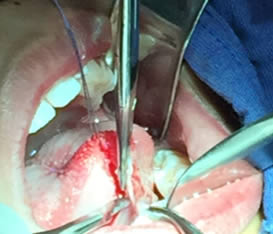

• Se eliminó el frenillo en su totalidad  con la ayuda de tijeras iris recta y hoja de bisturí del No. 15 así como todo el tejido residual fibroso correspondiente al frenillo. Se realizó genioplastia con pinza de mosco y disección roma para liberar adecuadamente la inserción frénica hasta la cara lingual de los incisivos inferiores. (Figuras  7, 8 y 9)

Figuras 7 y 8. Eliminación total del frenillo y genioplastia

Figura 9. Resultado obtenido después de genioplastia

• Se realizó prueba para ratificar la proyección lingual la cual fue exitosa (Figura 10).

Figura 10. Prueba exitosa de tracción lingual